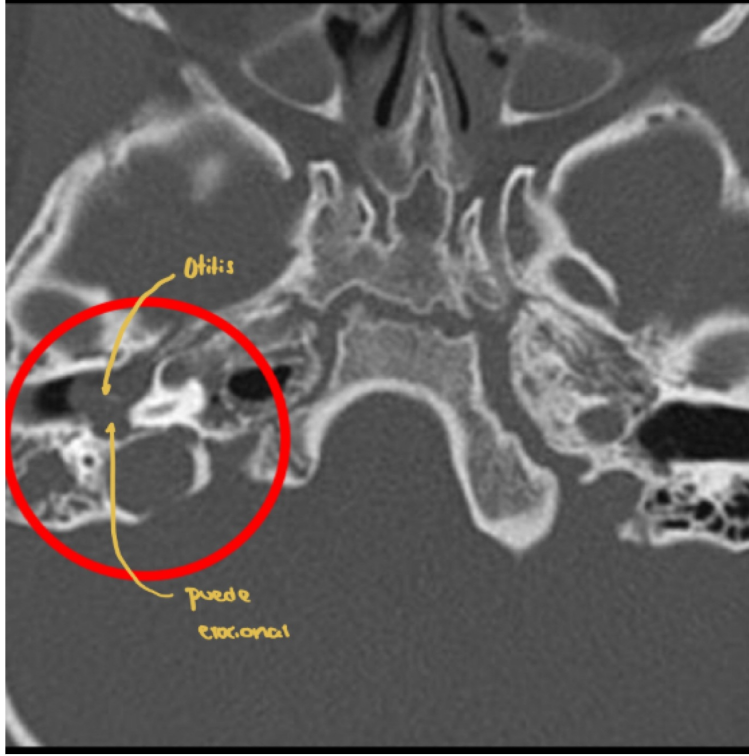

Mejor estudio de imagen y clave diagnóstica de otitis media

TC

Masa bien definida en oído medio (densidad intermedia) + erosiones osiculares o laberinticas

Q

Cuál es tu diagnóstico?

A

Otitis media